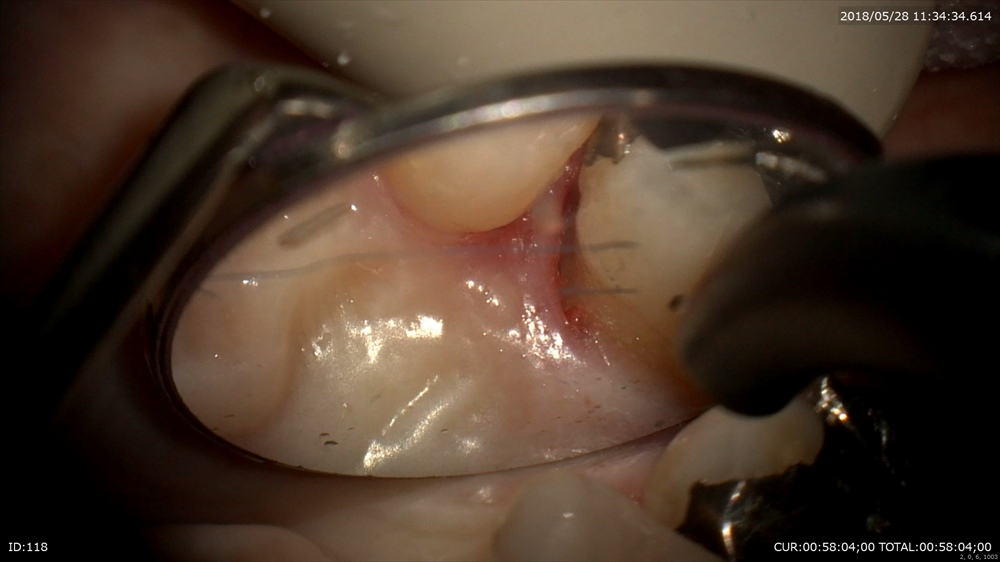

ここからキュレットでルートプレーニング

デブライドメント終了。歯周病は無痛で治る病気です。

隣の歯も

綺麗に

歯肉に傷をつけない

ここ

これが無痛で術後の安定のポイントです。